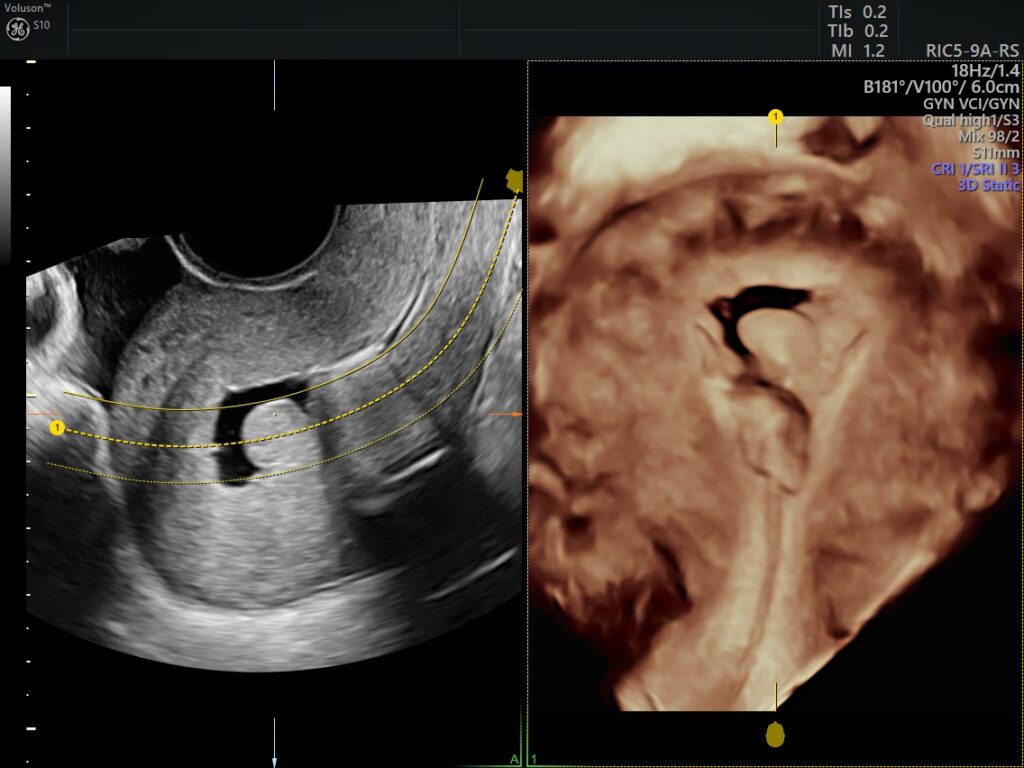

Endometriet er det medicinske udtryk for livmoderslimhinden, det lag af væv, der beklæder indersiden af livmoderen. Under en ultralydsscanning eller en MR-scanning (magnetisk resonansbilleddannelse) fremstår endometriet som en mørk linje, ofte omtalt som 'endometriestriben'. Dette er ikke en diagnose, men blot en beskrivelse af et normalt væv i kroppen.

Den mest almindelige og effektive metode til at måle endometriets tykkelse er en transvaginal ultralydsscanning. Denne procedure giver et klart og detaljeret billede af livmoderen og slimhinden. I tilfælde hvor en ultralydsscanning ikke giver et tilstrækkeligt klart billede, f.eks. på grund af livmoderens position eller andre medicinske tilstande, kan en MR-scanning anvendes.